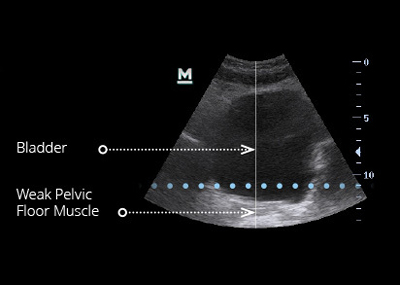

EMsella is a non-invasive treatment that uses high-intensity focused electromagnetic (HIFEM) technology to strengthen the pelvic floor muscles and improve bladder control. While you sit fully clothed on the EMsella chair, the technology delivers thousands of deep pelvic floor contractions—the equivalent of doing 11,000 Kegel exercises in just one 28-minute session.

Helps reduce symptoms of stress, urge, and mixed incontinence

The Emsella chair uses the same trusted HIFEM technology found in EMsculpt NEO. As you sit fully clothed, electromagnetic energy penetrates deeply into the pelvic floor area, inducing supramaximal pelvic-floor muscle contractions that would be impossible to perform voluntarily. These contractions re-train weak muscles, improve bladder control, and restore confidence.